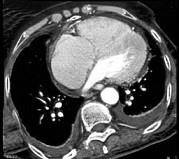

问题 男,38岁,反复咳嗽、咳痰伴发热15年余,痰结核菌素试验(—),结合CT图像,最可能的诊断是 ( )

选项 A.肺癌 B.肺结核 C.肺结节病 D.肺转移瘤 E.肺淀粉样变性

答案 E